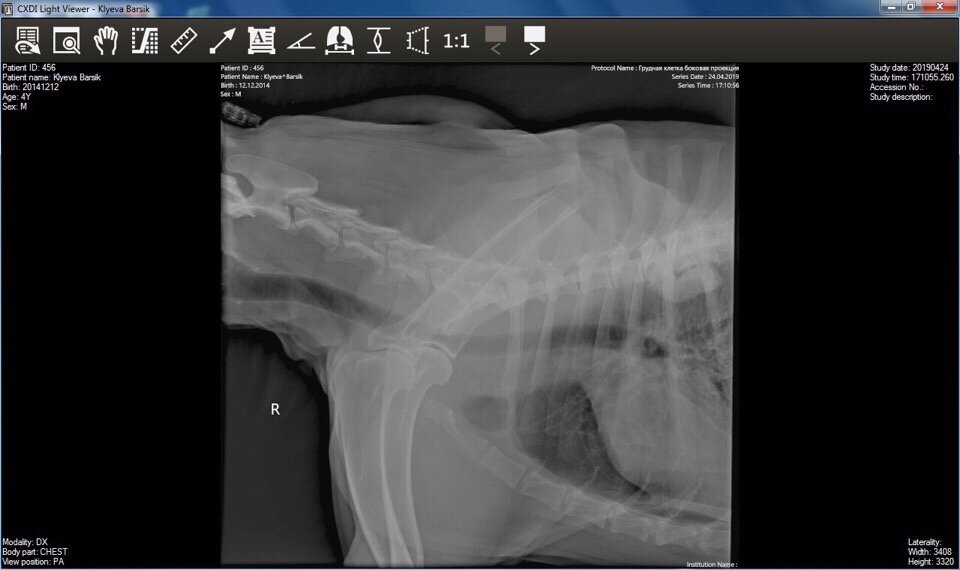

Одна из наиболее реализуемых целей для продолжения лечения Бархана была сделать новый рентген, про это мы уже говорили в статье: Пёс попал в надежные волонтеров, будем бороться!

Благодаря помощи добрых людей это получилось реализовать!

У собакина поставлен диагноз компрессия с Т5 до Т7 грудного позвонка. Логически был резкий удар, лопнули позвонки и образовалась костная мозоль, которая сжимает двигательный аппарат! Пёс Бархан: по извилистым тропам судьбы